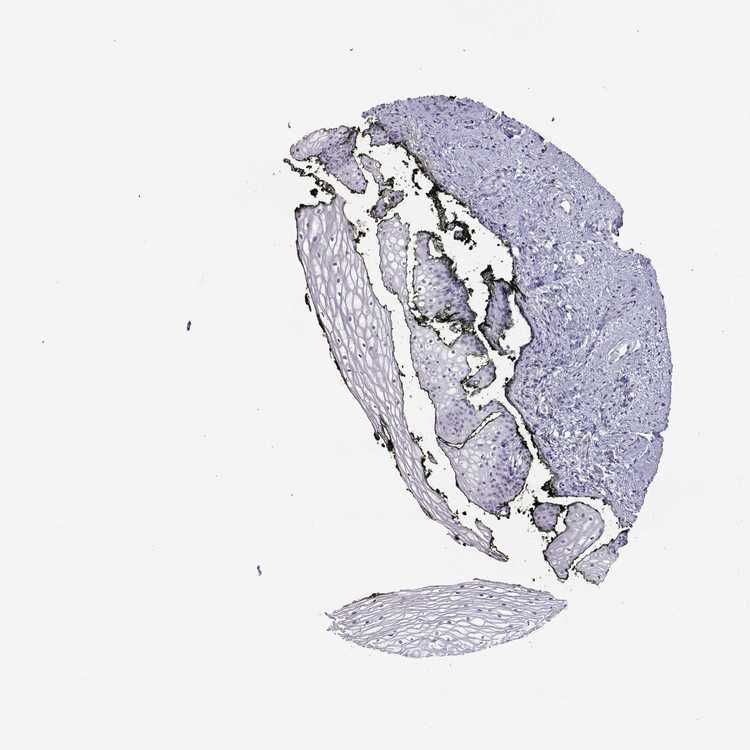

VAGINA - Antibody stainingi

Antibody staining in the annotated cell types in the current human tissue is reported as not detected, low, medium, or high, based on conventional immunohistochemistry profiling in selected tissues. This score is based on the combination of the staining intensity and fraction of stained cells.

Each image is clickable and will lead to virtual microscopy that enables deeper exploration of all samples and also displays staining intensity scores, fraction scores and subcellular localization as well as patient and tissue information for each sample.

Antibody HPA066142

Squamous epithelial cells Not detected